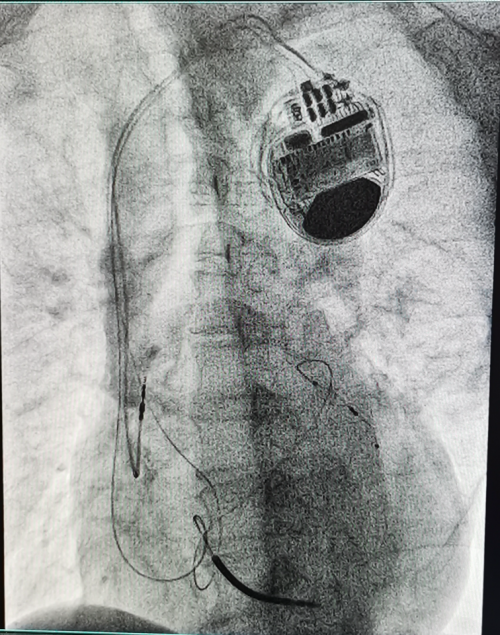

CRT-D重启“心”生,重获“心”力 ——衡阳市第一人民医院成功开展衡阳地区首例3.0T MRI兼容CRTD植入术

(通讯员 彭彦 邹勇)近日,衡阳市第一人民医院心血管内科专家团队成功为一名终末期心力衰竭患者,实施了衡阳地区首例3.0T磁共振(MRI)兼容心脏再同步化治疗心律转复除颤器(CRT-D)植入术。此项技术的开展,填补了区域内该领域的技术空白,标志着该院心脏起搏与电生理诊疗技术实现了跨越式提升,为当地心衰患者带来了新的生命守护方案。

作为心力衰竭治疗的“终极武器”之一,CRT-D(俗称“三腔除颤器”)是集治疗与防护于一体的高端医疗设备。它既具备心脏再同步治疗(CRT)的核心作用,又拥有植入式心律转复除颤器(ICD)的急救功能,为患者的生命安全拴上“双保险”。此次手术的关键突破在于“3.0T MRI兼容”。传统CRTD设备因受电磁兼容性限制,患者术后无法接受高磁场强MRI检查,而MRI作为多种疾病(如肿瘤、脑血管疾病)的重要诊查手段,其检查限制往往给患者后续诊疗带来极大困扰。3.0T MRI兼容型CRTD的成功应用,彻底打破了这一壁垒,患者术后可自由接受3.0T MRI检查,既不影响设备正常工作,又能获得全面精准的后续诊断,极大提升了治疗的安全性与便利性。